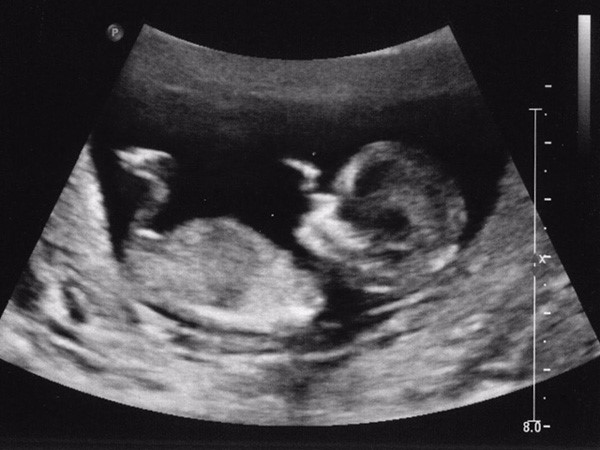

Siêu âm thai 12 tuần là một trong những mốc rất cần thiết và quan trọng đối với các mẹ bầu. Siêu âm trong thời điểm này giúp các bà mẹ nắm rõ mọi vấn đề về sự phát triển của thai nhi. Để từ đó các mẹ sẽ có được chế độ dinh dưỡng khoa học, phù hợp để thai phát triển tốt nhất.

Thực hiện siêu âm thai ở tuần 12 sẽ giúp các mẹ nắm được sự phát triển của thai nhi như thế nào? Đồng thời cũng sẽ giúp được phát hiện những dị tật ở thời điểm này. Nếu có dị tật thì các bác sĩ chuyên khoa sẽ đưa ra những phương pháp can thiệp phù hợp nhất.

Ở thời điểm tuần 12 lúc này thai nhi đang phát triển mạnh mẽ với những chỉ số vượt bậc. Thông qua siêu âm ở thời điểm này các mẹ sẽ nắm được rất nhiều chỉ số về sự phát triển của thai nhi.

Khi thai nhi phát triển đến tuần thứ 12 khi siêu âm các bác sĩ sẽ đo được độ mờ vai gáy. Ngoài ra, còn có thể khảo sát được những nhiễm sắc thể bất thường của thai nhi. Mỗi nhiễm sắc thể bất thường sẽ là dị tật của thai nhi như dị tật tứ chi, mắc hội chứng Down, dị dạng về tim hay thoát vị cơ hoành….

Tuy nhiên, với một số dị tật và biến chứng thì các mẹ cần phải làm thêm nhiều xét nghiệm khác để khẳng định về bệnh. Khi thai nhi 12 tuần thì các bác sĩ sẽ siêu âm kỹ lưỡng không chỉ siêu âm đen trắng mà còn siêu âm màu siêu âm 4D để nắm rõ những chỉ số cơ thể của thai nhi.

Ngoài ra, những dấu hiệu về thai không bình thường như mẹ mang đa thai cũng sẽ phát hiện ra. Vì vậy, thời điểm này các mẹ không nên bỏ qua siêu âm thai nhi.